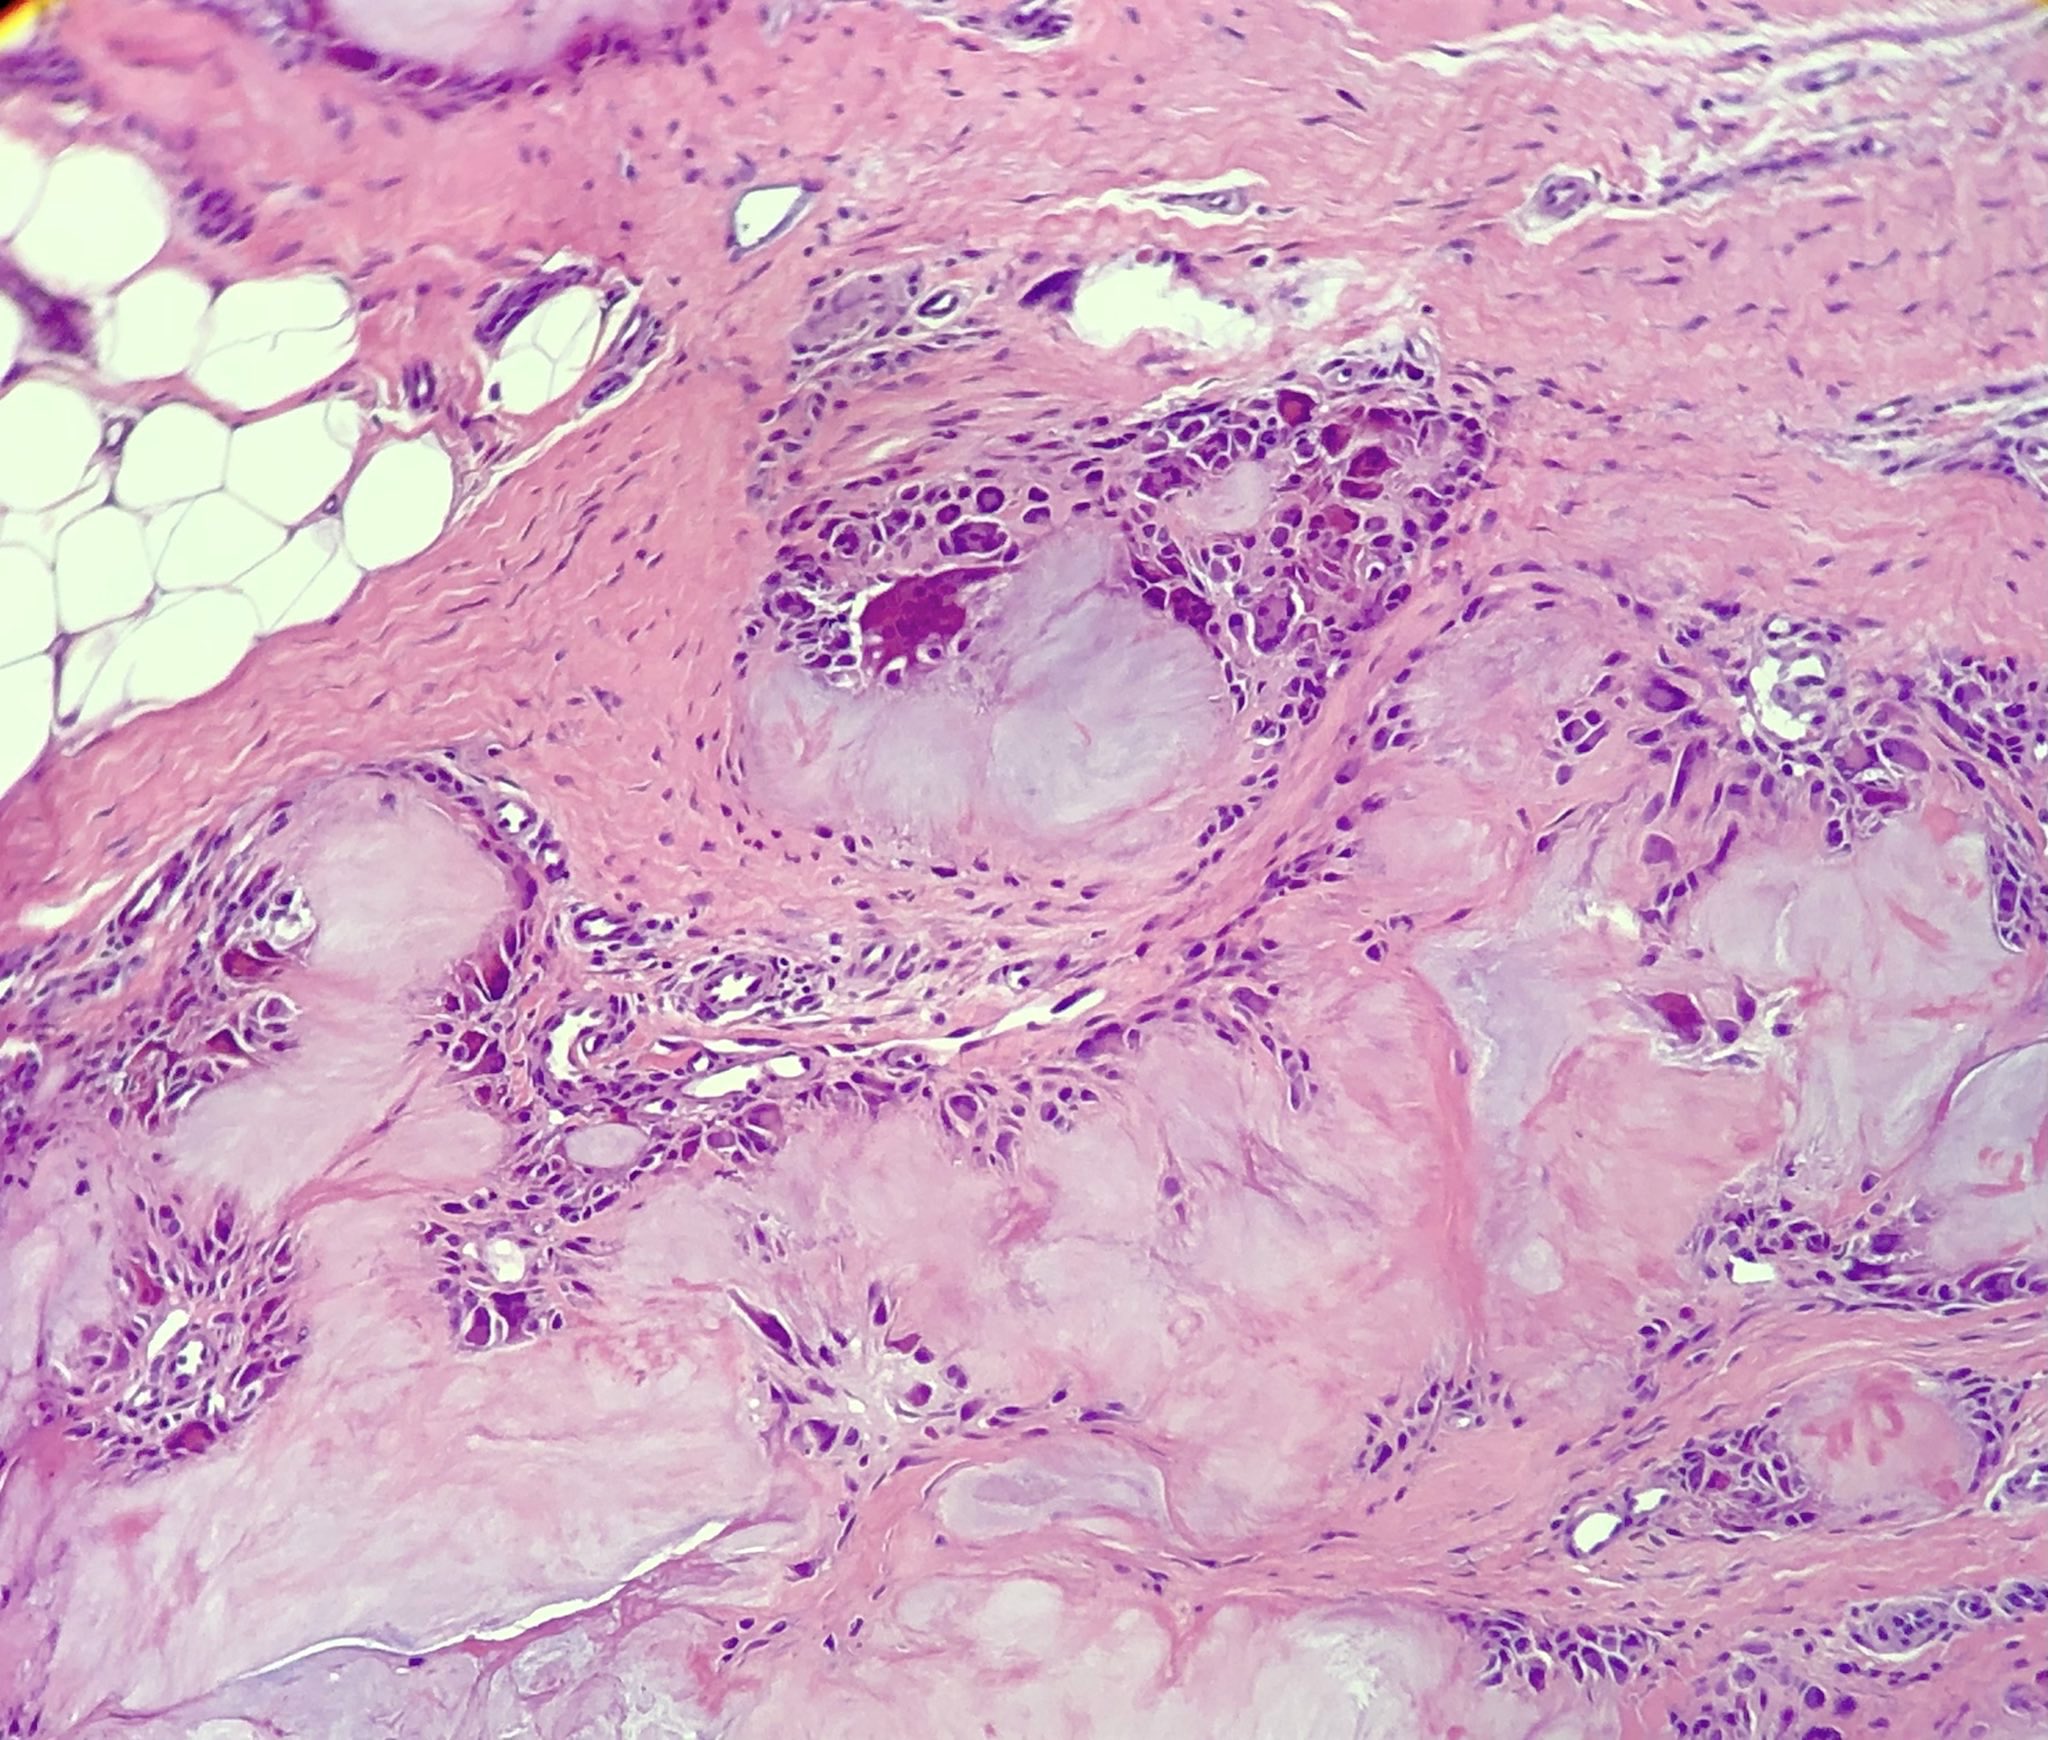

Microscopic (histologic) description

- Gout tophus:

- Nodular aggregates / granuloma-like appearance consisting of acellular, amorphous, pale eosinophilic material surrounded by palisading arrangement of histiocytes and multinucleated giant cells (Dermatol Online J 2015;21:13030)

- Feathery appearance in some deposits due to empty needle shaped spaces (Skeletal Radiol 2020;49:1325)

- Presence of monosodium urate crystals (MSU) is diagnostic

- Needle-like crystals that measure 5 - 25 micrometers in length

- Synovium changes:

- Affected synovium shows villous hyperplasia and synoviocyte hypertrophy and hyperplasia

- Typical chronic synovitis with mononuclear leukocyte infiltrate

- Urate crystals are also identified (Medicine (Baltimore) 1978;57:239)

- Bone and cartilage changes:

- MSU crystal deposition in bone is associated with cystic erosion, secondary cortical fracture, destruction of bony trabeculae, osteonecrosis and infiltration of trabecular spaces by chronic inflammatory cells

- Other changes include fibrotic bone marrow with proliferation of dilated capillaries, osteoclastic and osteoblastic activity and new bone formation (BMC Musculoskelet Disord 2019;20:140)

- Affected cartilage appears fibrillated, eroded and fissured

- Granulation tissue formation, fibrous replacement and chondronecrosis may occur (BMC Musculoskelet Disord 2019;20:140)

Microscopic (histologic) images